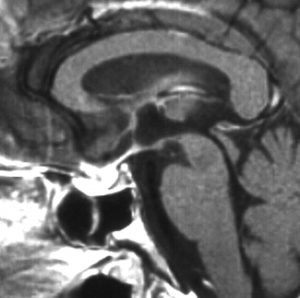

germinomaの視床浸潤:ミッキーマウスの耳

松果体ジャーミノーマは両側視床に浸潤して視床浮腫を生じます。真ん中に第3脳室後半部の割れ目が残っているのが特徴的な所見です。ミッキーマウスの耳みたいになります。かなり特異的な所見であり診断に有用です。右下は治療後です。